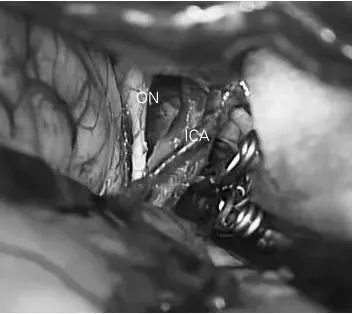

显示夹闭动脉瘤的显微图像。在颈内动脉表面未观察到明显异常。ICA:颈内动脉,ON:视神经。